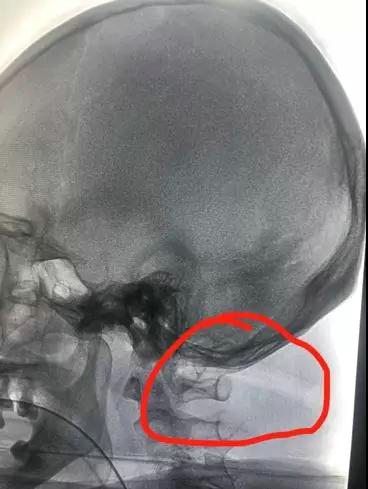

神经外科复合手术间,患者先进行血管造影

患者因树枝插在枕部无法平躺,给麻醉科带来极大困难。麻醉医生刘晓媛顶住压力侧卧位下插管成功。介入科刘健医生也是侧卧位下为患者进行了DSA实时血管造影,显示椎动脉未受到影响。

术中DSA造影显示:椎动脉位于树枝边缘,未受到影响